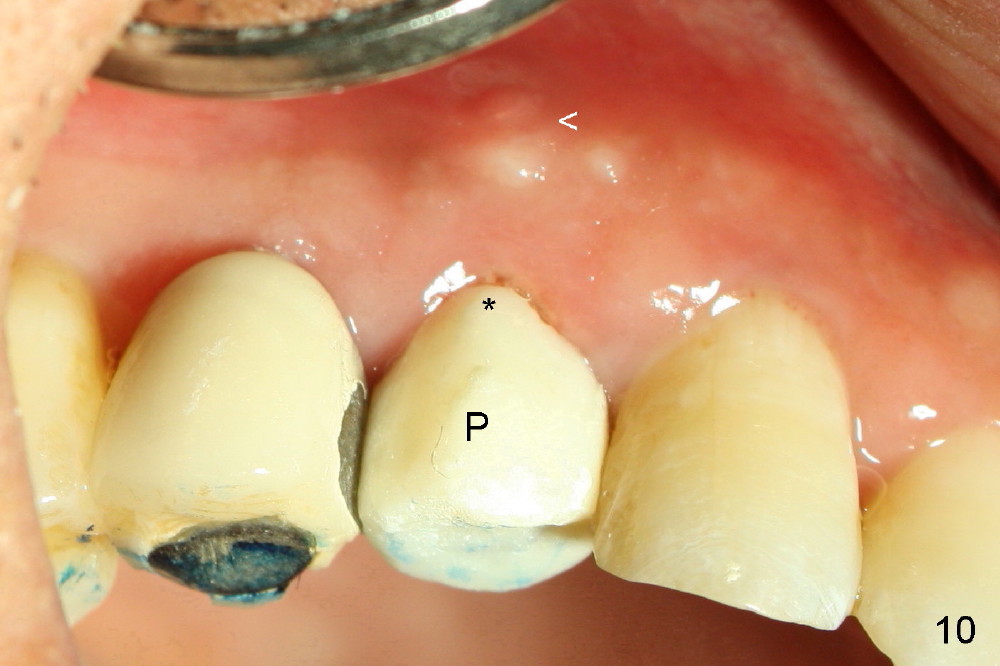

As expected, the collagen dressing is dislodged when the perio dressing is off; fortunately the bone graft remains in place 7 days postop (Fig.9 *). To keep the bone graft in place, an immediate provisional (Fig.10 P) is fabricated and cemented; its margin (*) covers the graft. There is no occlusal contact in centric and lateral excursion. The patient is asked not to use this crown for 3 months.